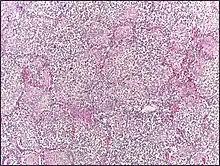

Lobar pneumonia usually has an acute progression. Classically, the disease has four stages:[1]

- Congestion in the first 24 hours: This stage is characterized histologically by vascular engorgement, intra-alveolar fluid, small numbers of neutrophils, often numerous bacteria. Grossly, the lung is heavy and hyperemic.

- Red hepatization or consolidation: Vascular congestion persists, with extravasation of red blood cells into alveolar spaces, along with increased numbers of neutrophils and fibrin. The filling of airspaces by the exudate leads to a gross appearance of solidification, or consolidation, of the alveolar parenchyma. This appearance has been likened to that of the liver, hence the term "hepatization".

- Grey hepatization: Red blood cells disintegrate, with persistence of the neutrophils and fibrin. The alveoli still appear consolidated, but grossly the color is paler and the cut surface is drier. This is when death typically occurs in severe cases.

- Resolution (complete recovery): The exudate is digested by enzymatic activity, and cleared by macrophages or by cough mechanism. Enzymes produced by neutrophils will liquify exudates, and this will either be coughed up in sputum or be drained via lymph.